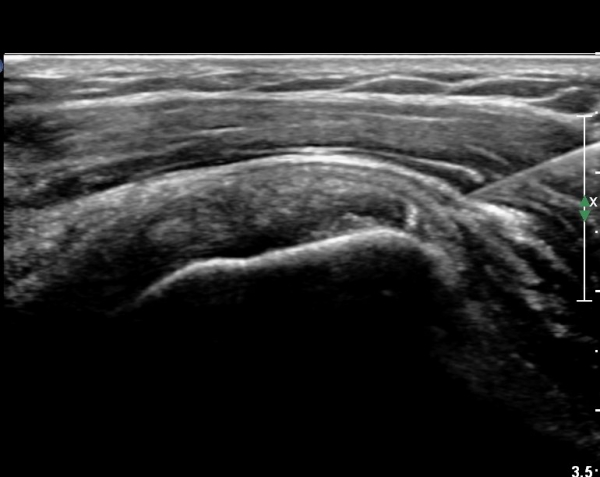

°ß°©ÇϱٰǠ Á¾´Ü¸é°Ë»ç¿¡¼­ °ÇºÎÂøºÎ¿¡ ÀÛÀº ¼®È¸È­À½¿µÀÌ °üÂûµÊ(»çÁø 2).